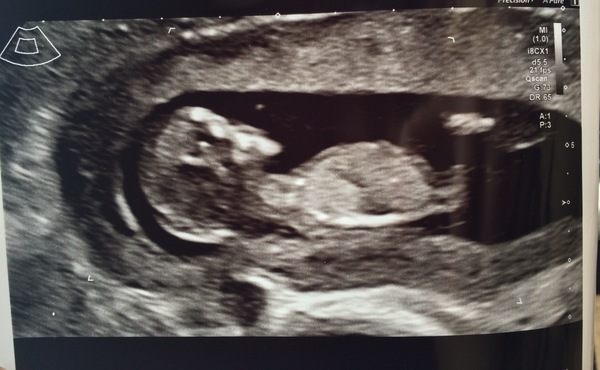

Shook2018 · 22/02/2018 19:26

Oops jellybean didn't appear! Here they are...

Great scan pic shook!